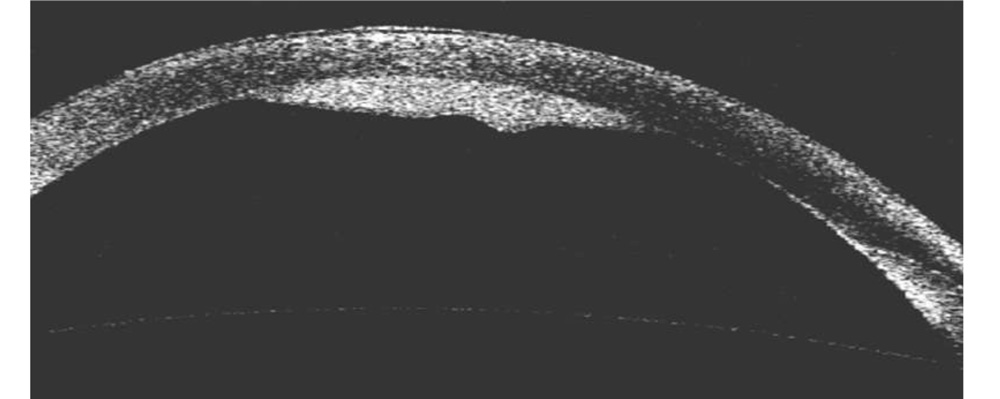

A 77 years old male patient came with the complaints of white coloured opacity in the left eye noticed since 1 week. He had undergone phacoemulsification surgery in his left eye 19 months back. His best corrected vision was 6/6 in the right eye and 6/9 in the left eye. On slit-lamp examination, an area of localized bullous DMD of about 4 mm in diameter was noted. It was present in the inferior half of the cornea, with the upper limit of the detachment bisecting the pupil (Figure 1). The space between the stroma and the descemet membrane (DM) was filled with whitish turbid fluid. The fluid was more opaque in the inferior three-fourth of the space with relatively transparent fluid filling up the remaining upper part, thus resembling a hypopyon. AS- OCT confirmed the DMD with fluid filled in the space (Figure 2). There were no signs suggestive of inflammation. A posterior chamber intra-ocular lens was present in both the eyes. The rest slit-lamp examination of the right eye was normal. The fundus examination was normal.

Figure 2: AS-OCT image showing DMD with fluid filled space.

Figure 3: Day 1 post-operative AS-OCT image showing increase in corneal thickness, irregular DM and small DMD at the incision site.